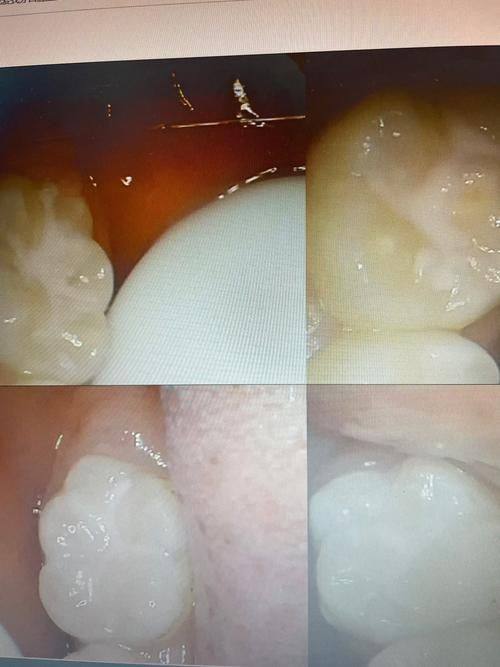

20. 牙冠:1000-5000元

13. 烤瓷牙:800-3000元

8. 根管治疗:300-1500元